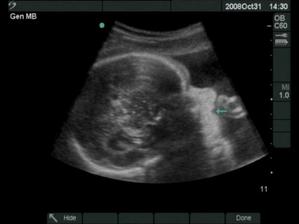

Moje tehotenstvo a naše bábätká

18.12.2008 prišli na svet o 3 týždne skôr naše krásne dvojičky. Ako prvá predrala cestu svojmu bratčekovi Laura, ktorá išla hlavičkou. Prišla na svet 12:53 a vážila 2720 g a merala 46 cm. Marko mal výjsť hneď na to zadočkom, ale keď zistil že sa mu uvoľnilo miesto asi si to rozmyslel a rozhodol sa v brušku zostať a spriečil sa. Pán doktor ho musel síce trochu povykrúcať aby ho dostal von, ale našťastie sa mu to podarilo a nemuseli maminu po normálnom pôrode aj rezať 🙂 Svetlo sveta uzrel Marko 13:03 a vážil 2890 g a meral 48 cm.